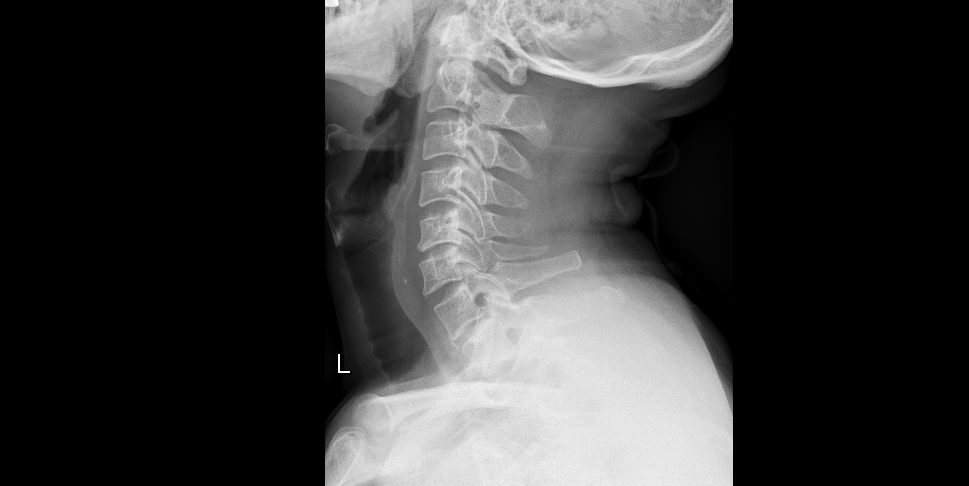

案例一术前

“经过颈椎磁共振检查,发现你的颈5/6椎间盘髓核突出压迫脊髓,并伴有椎管狭窄”,接诊的刘汝专主任说道。结合症状、体格检查和影像学检查,排除了颅脑问题后诊断陈先生为脊髓型颈椎病引起的下肢乏力和步态不稳。经科室讨论,刘汝专团队决定采用“颈椎前路颈5/6椎间盘切除+Cage植骨融合内固定术”治疗陈先生。

“这类手术方法在颈椎手术中属于比较经典的颈椎微创手术,它能够对颈椎间盘髓核突出压迫脊髓进行直接摘除减压,同时也可以通过椎间融合器植入恢复一定的颈椎生理曲度,而且术口一般长度约为3-4cm,愈合快出血量少”,刘汝专主任告诉陈先生和其家人。术后第一天,陈先生感觉自己的下肢“如释重负”,乏力症状明显改善,走路也比术前稳了很多,术后第七天术口拆线后就出院回家了。